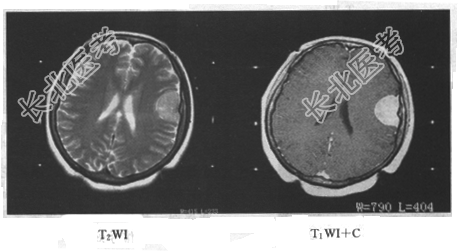

- 单项选择题患者,女, 34岁。头痛数年,头颅MRI平扫及增强扫描, 如下图所示最可能的诊断是

A、脑膜瘤

B、星形细胞瘤

C、生殖细胞瘤

D、动脉瘤

E、三叉神经瘤